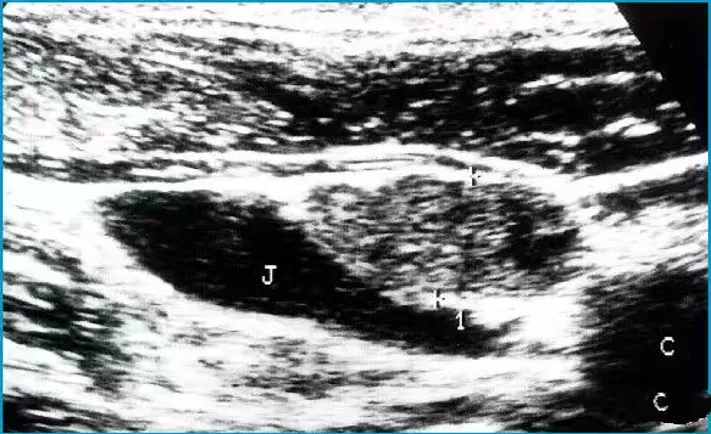

病例:右侧颈部肿痛3天,颈部可触及多个痛性结节。

超声描述:右侧颈部Ⅲ、Ⅳ区可见多发肿大的淋巴结,大者约21x6mm,呈椭圆形,皮质增厚,髓质居中,内部血流信号明显增多,呈放射状分布。